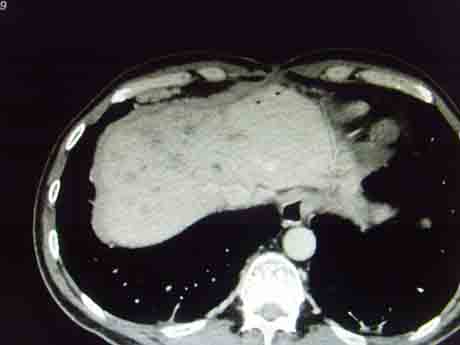

CT51143:胆管癌是否复发?

本帖最后由 cefcmj 于 2015-9-10 21:10 编辑 男,52岁,肝门部胆管癌术后1年,胆肠吻合,胆管癌是否复发?

可疑复发,建议增强

可疑复发,建议短期内复查